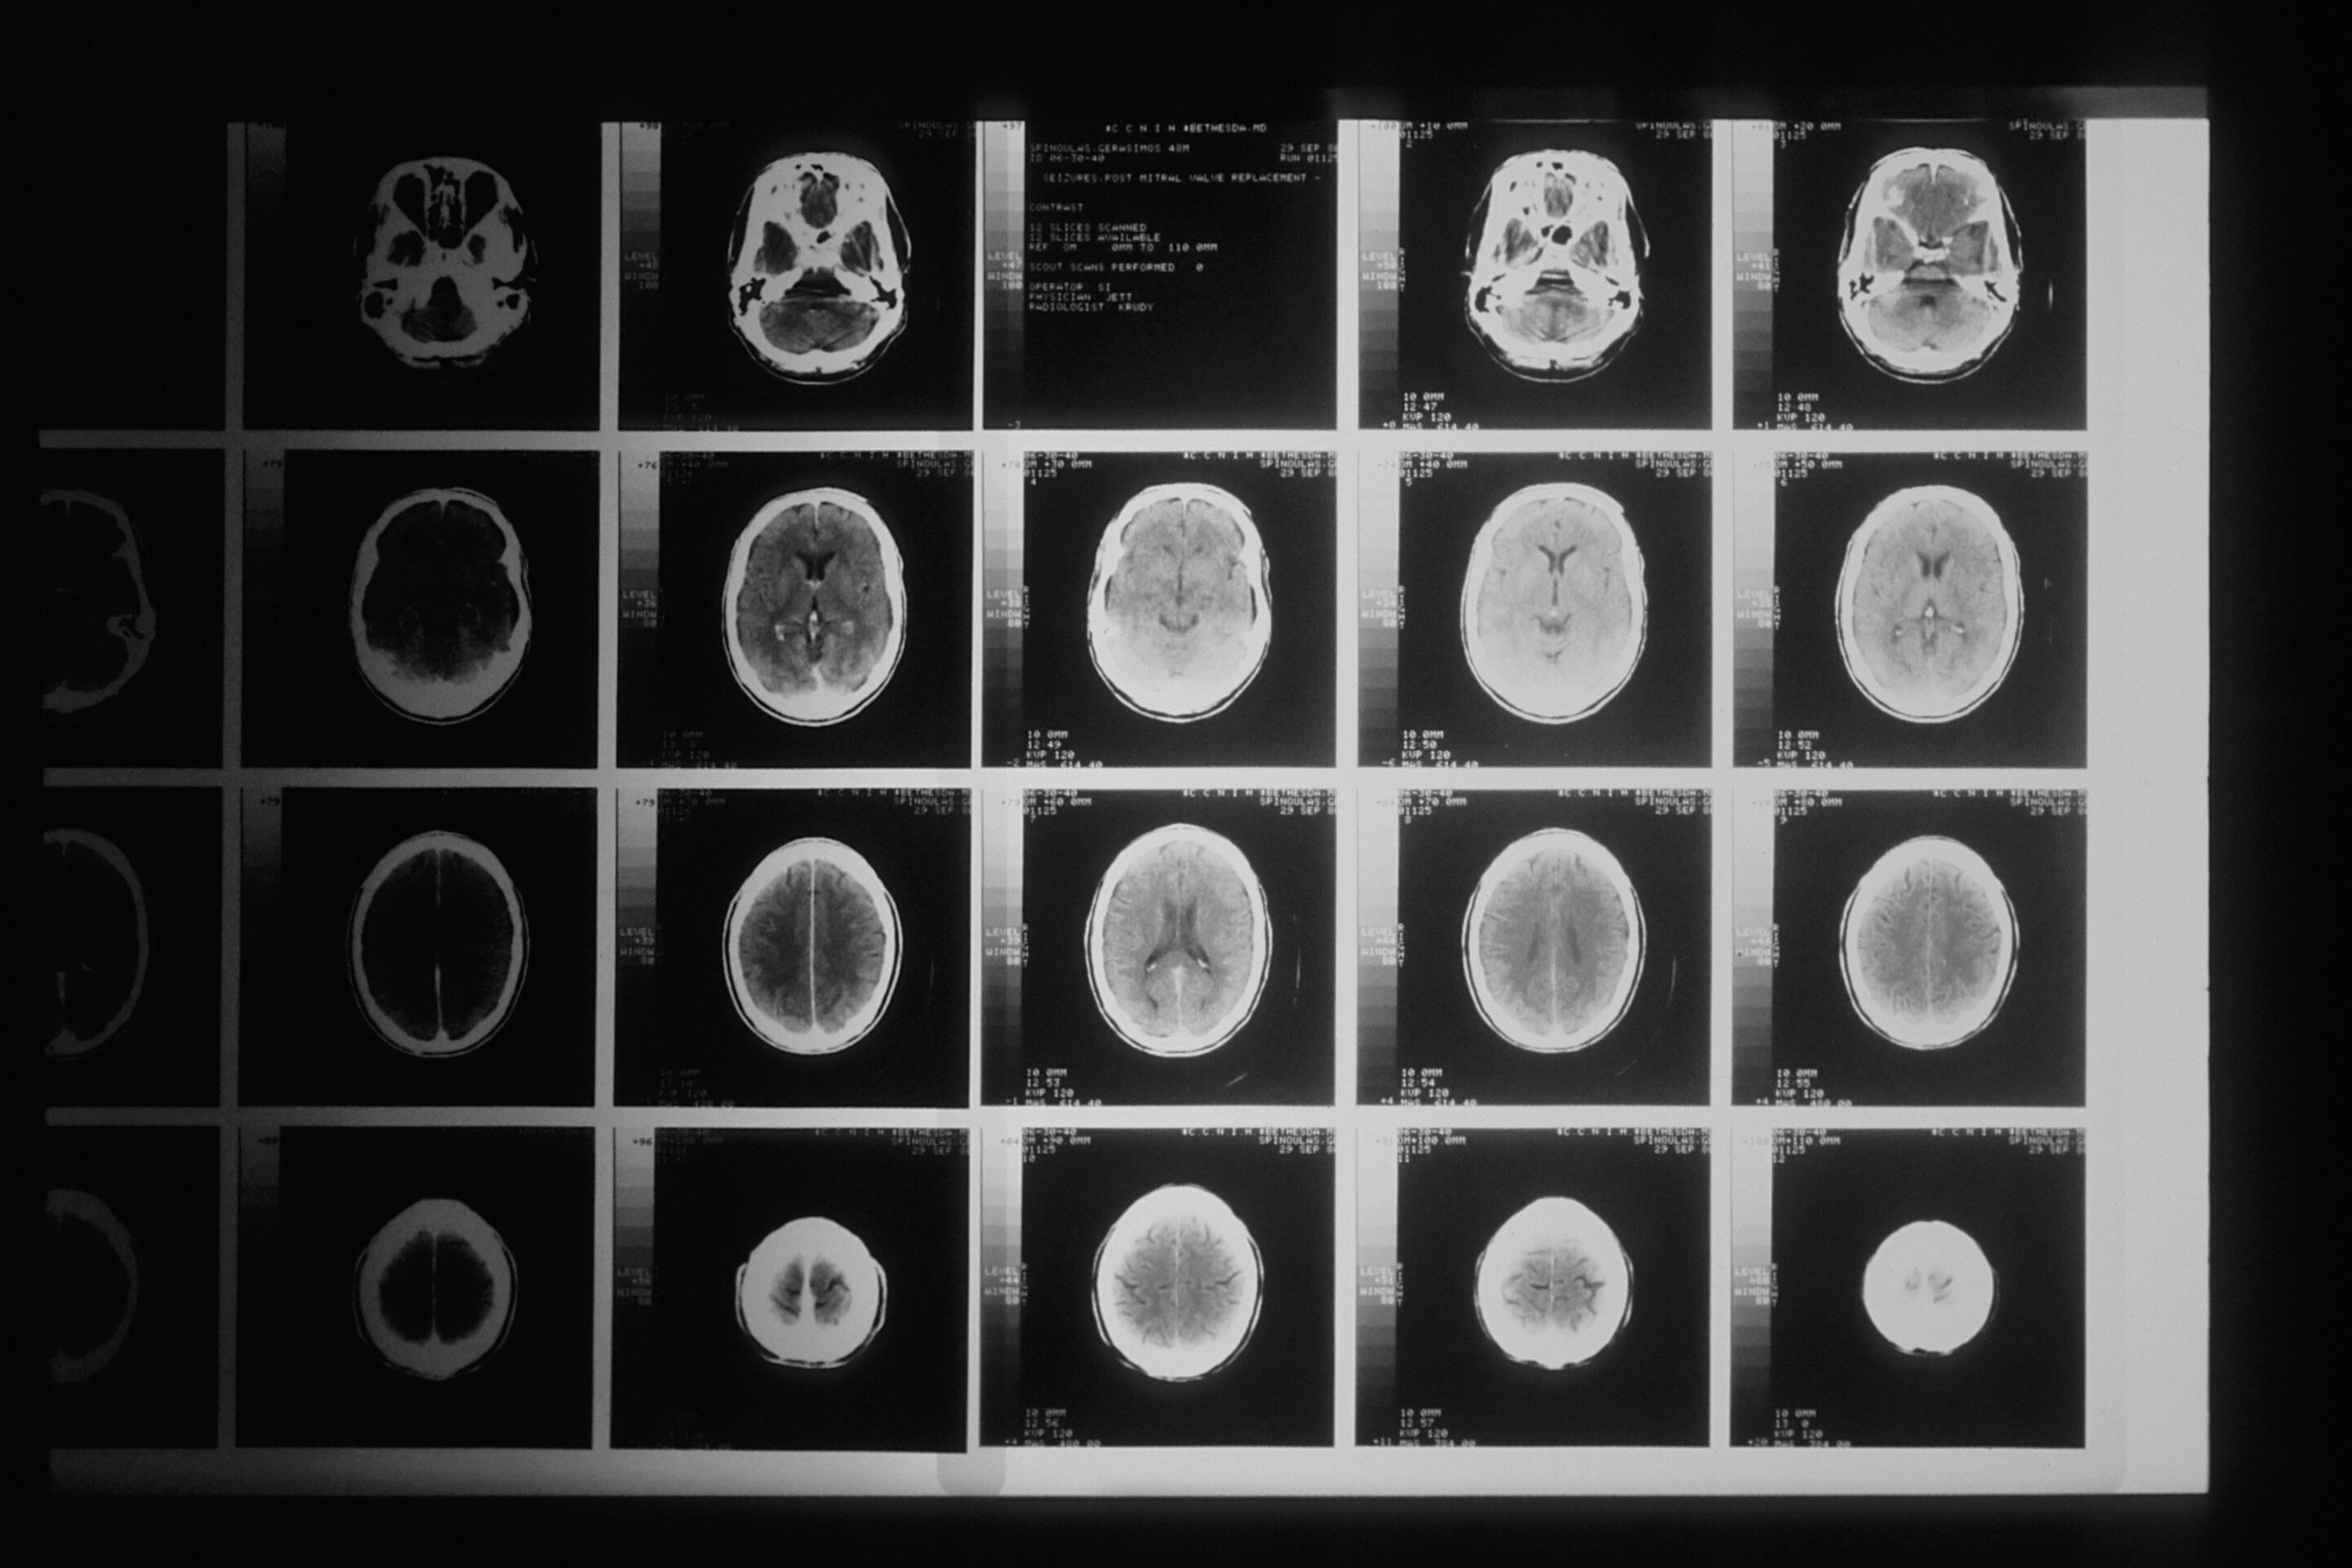

Cercetătorii au analizat înregistrările din spitalele din Tasmania și decesele din perioada 2007-2020, identificând aproape 5.000 de cazuri de accident vascular cerebral în premieră între 2015 și 2020.

Studiul a arătat că indivizii din grupul cu cel mai scăzut nivel socio-economic aveau un risc cu 33% mai mare de a suferi un accident vascular cerebral în comparație cu cei din grupul cu cel mai înalt nivel socio-economic.

Studiul a mai constatat că factorii de risc pentru accidentul vascular cerebral, precum diabetul, tensiunea arterială ridicată și bolile de inimă, erau mai frecvente în comunitățile dezavantajate.